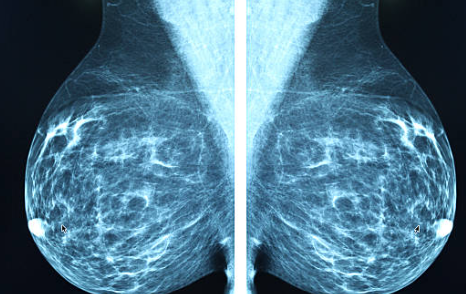

์ ๋ฐฉ์ดฌ์์ ๋ก 40์ธ ์ดํ์๋ ์ ๊ธฐ์ ์ธ ์ ๋ฐฉ ์ดฌ์์ ํตํด ์กฐ๊ธฐ ๋ฐ๊ฒฌ์ ํ์จ์ผ ํฉ๋๋ค.